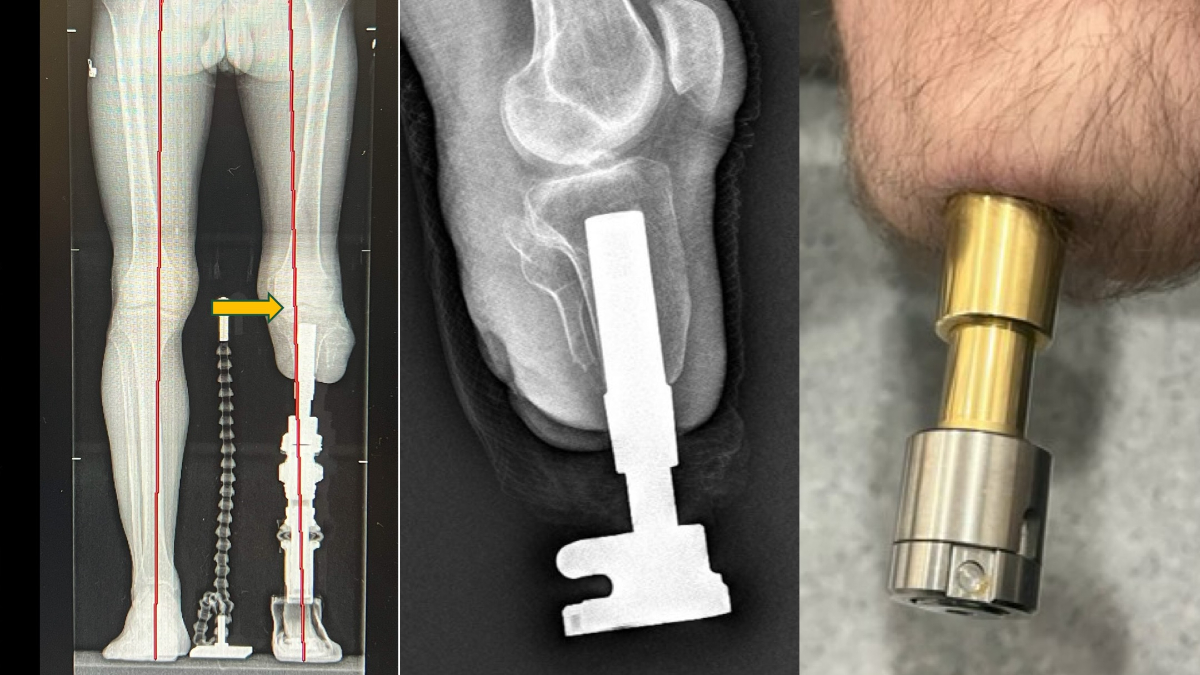

Kemiğe yerleştirilen implantlarla daha doğal ve konforlu bir yürüyüş sunan bu yöntem Türkiye’de de uygulanıyor.

Bu yöntemde, kemiğe yerleştirilen implant sayesinde yük doğrudan kemiğe aktarıldığından, çok daha doğal ve konforlu bir yürüyüş mümkün oluyor.

Kullanım süresi hakkında da bilgi veren Prof. Dr. Kara, “Bu protezlerde yalnızca dış parçalar zamanla değiştiriliyor. Suya dayanıklı modeller sayesinde hastalar denize bile girebiliyor. Günlük hayatlarına yakın bir yaşama dönüş mümkün oluyor” dedi.